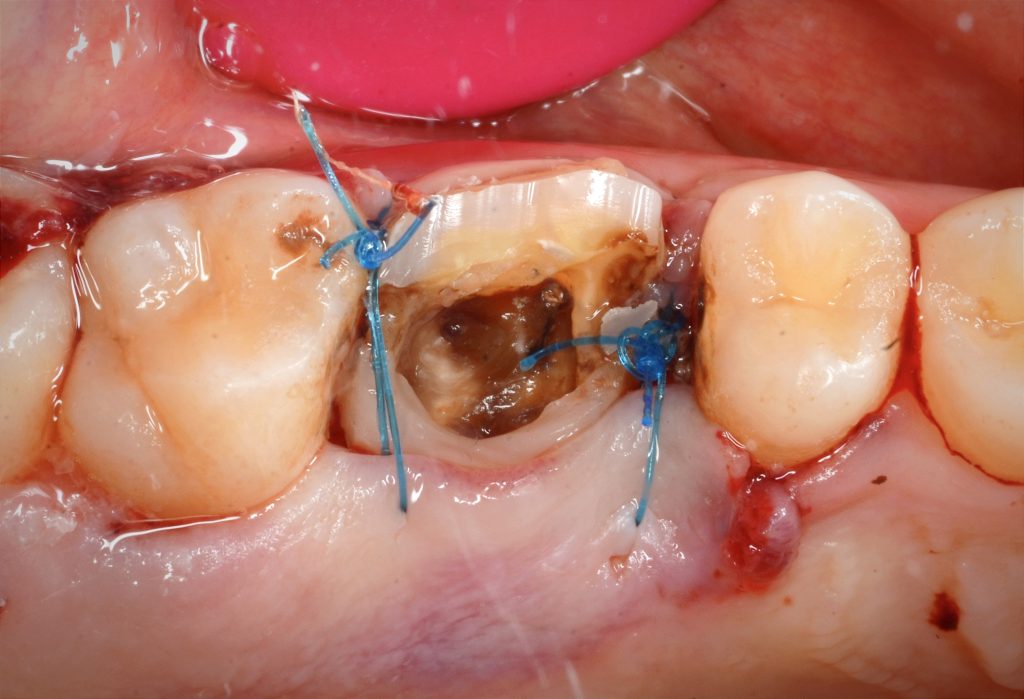

Crown lengthing procedure

Isolation to build up and dme

Ribbond around palatal wall to give more strength